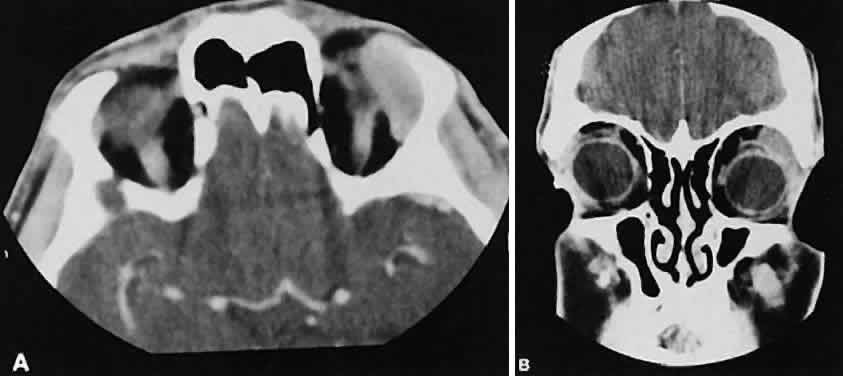

Graves' orbitopathy probably represents the most frequent cause of proptosis and EOM enlargement. The CT findings are fairly stereotyped and typically display various degrees of EOM enlargement (Fig. 7). The inferior rectus muscle usually is affected earliest, followed by the medial rectus, superior rectus, and finally the lateral rectus muscle. Rootman and colleagues13 noted more frequent involvement of the superior rectus/levator and medial rectus muscles than what had been reported previously with Graves' orbitopathy. These muscles can be affected in isolation, with the exception of the lateral rectus. To the best of our knowledge, isolated lateral rectus enlargement has not been reported in Graves' orbitopathy and in our experience usually is associated with a sphenoid wing meningioma.

Fig. 7. Graves' orbitopathy with two variations. Axial (A) and coronal (B) views show symmetric fusiform enlargement of the extraocular muscles with tapered muscle insertions. Note the predominant enlargement of the inferior, medial, and superior rectus muscles with lesser involvement of the lateral rectus muscle, a frequent pattern of enlargement in Graves' orbitopathy. Axial (C) and coronal (D) views of Graves' orbitopathy with expansion of retrobulbar ground substance and relative sparing of the extraocular muscles.